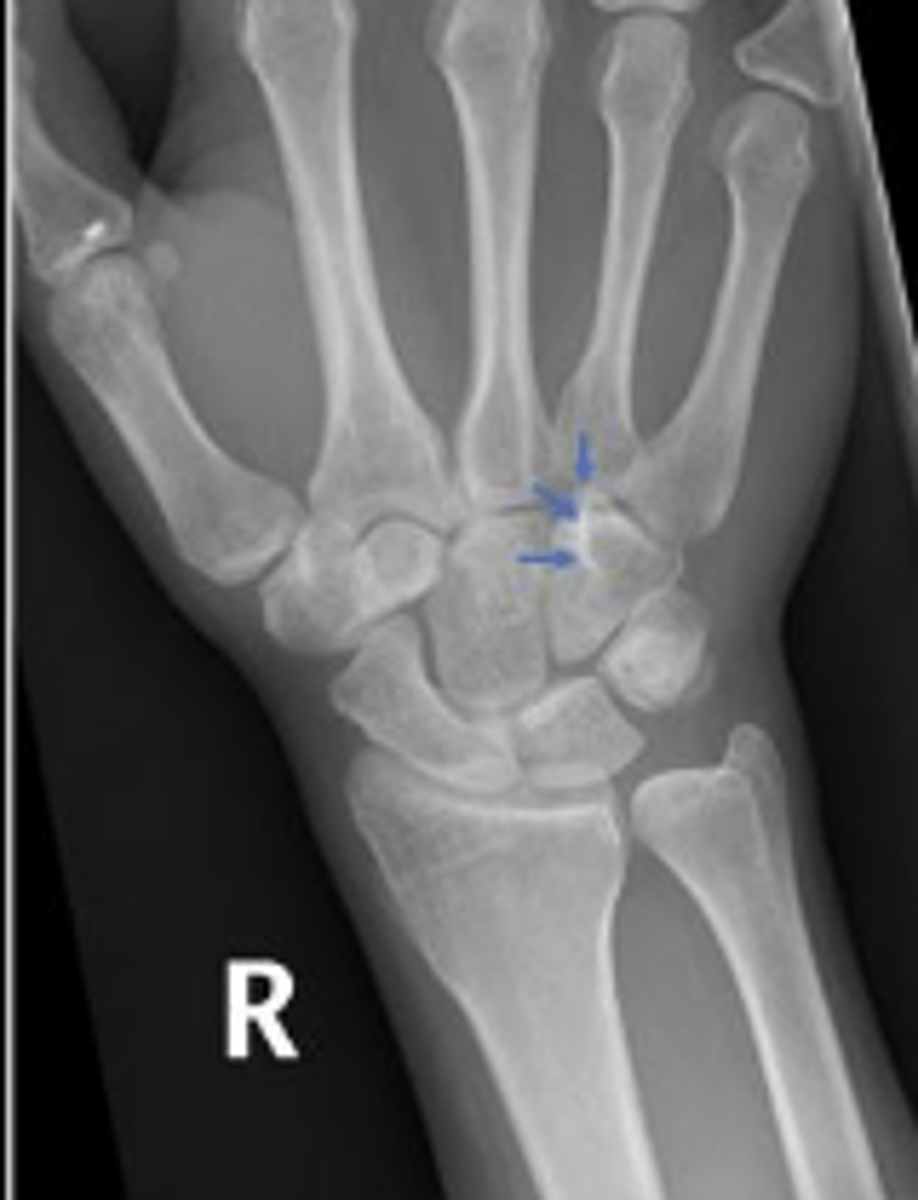

Hook of the right hamate

What are the arrows pointing to?

Right lunate

What is outlined?

Right hamate

Base of the 2nd right metacarpal bone

What is the arrow pointing to?

3 arcs of carpal alignment

What is the name of the assessment

Proximal cortical aspect of the first (proximal)

carpal row (ARC 1)

What are the landmarks for the most proximal line in the assessment?

Distal cortical aspect of the first (proximal) carpal

row (ARC 2)

What are the landmarks for the most middle line in the assessment?

Proximal cortical aspect of the second (distal)

carpal row (ARC 3)

What are the landmarks for the most distal line in the assessment?

SLAC wrist; carpal dislocation, carpal fracture

Name 2 conditions that will result in an alteration of the assessment?